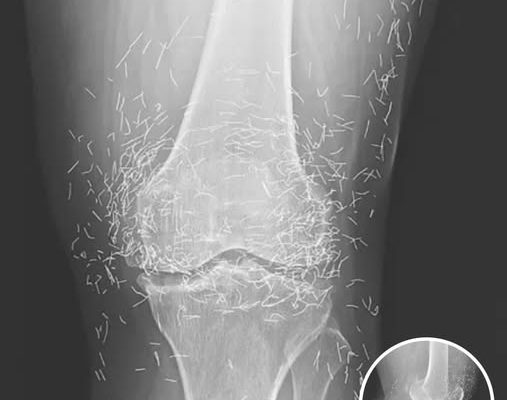

In this case, the needles were intentionally left in her body as part of a long-term treatment strategy. Some practitioners believe that leaving gold needles or threads in place can provide ongoing stimulation to the affected area. However, medical professionals warn that this approach carries significant risks.

Dr. Ali Guermazi, a radiology expert from Boston University not involved in the case, explained that the human body can react negatively to foreign objects. Inflammatory responses, tissue damage, and infections are potential complications. Additionally, the embedded needles can interfere with medical imaging, making diagnosis more difficult.

One of the most serious risks comes with MRI scans. The powerful magnetic forces used in MRIs can cause metal objects to move within the body, possibly leading to punctured blood vessels or other life-threatening injuries. This makes metal implants a critical concern for patients who may need future imaging.